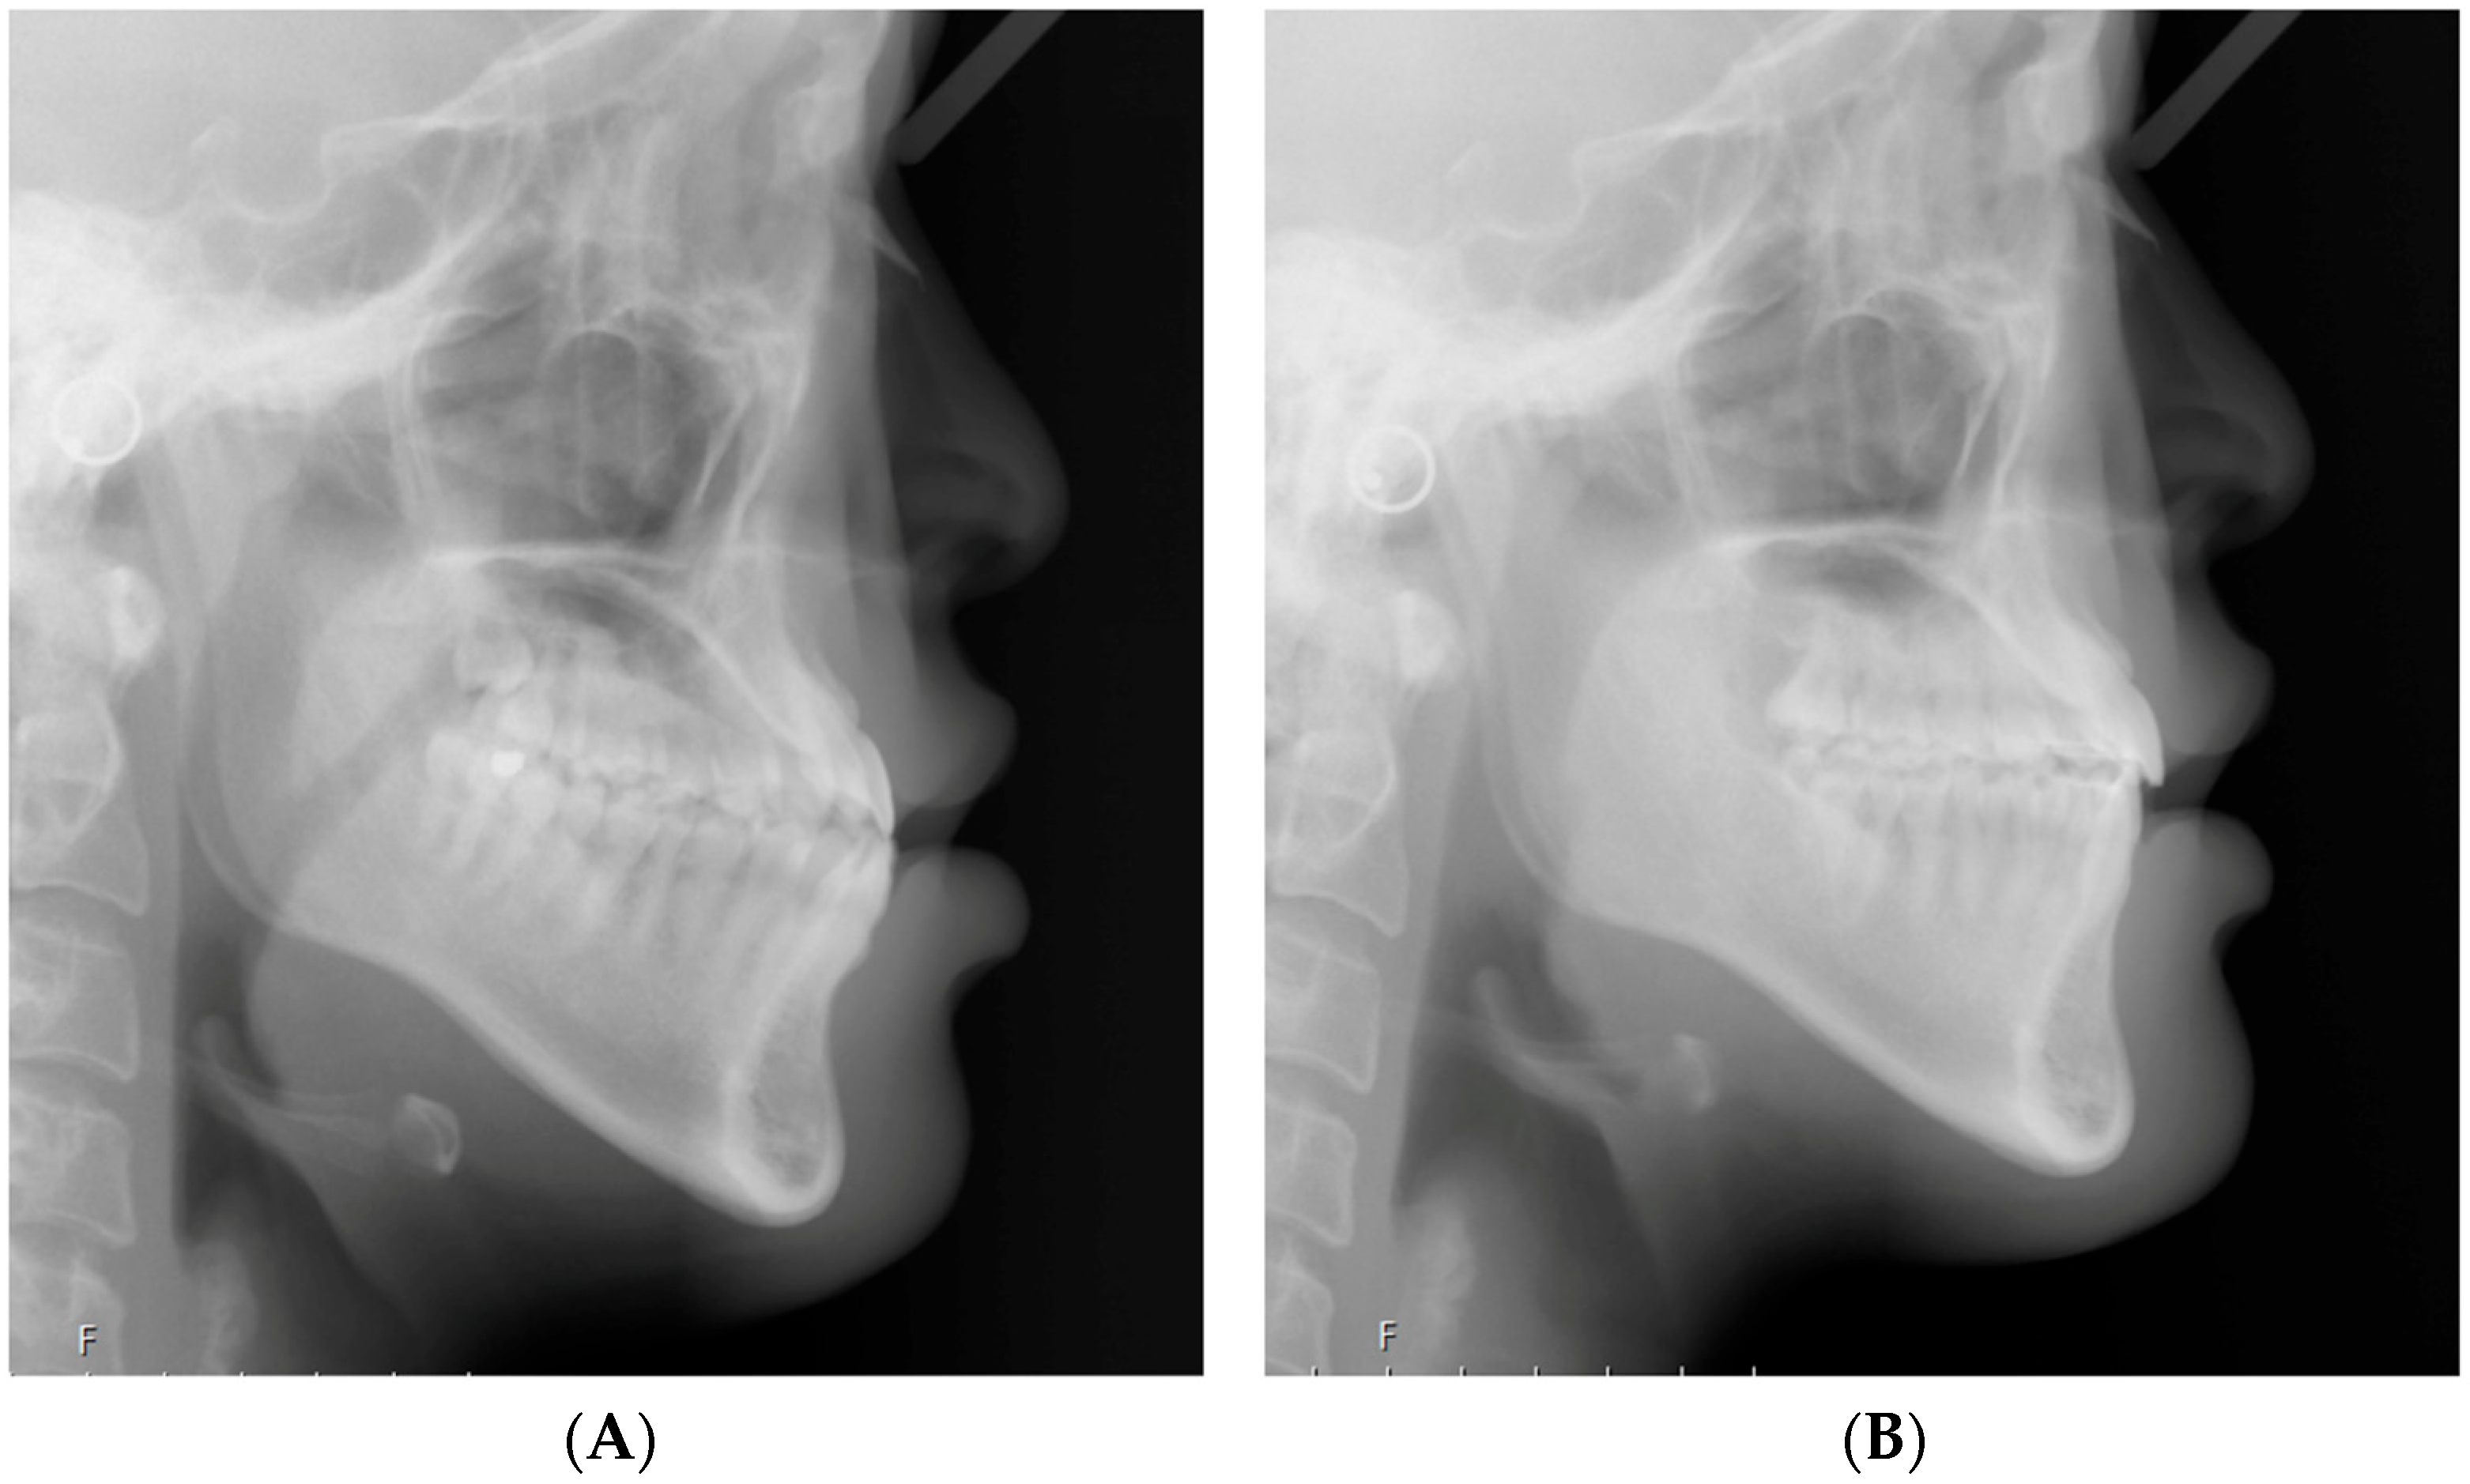

2.2. Cephalometric Analysis